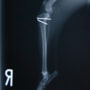

■ 症例24 キャバリア 7か月

左右膝蓋骨内方脱臼(左:グレードⅣ 右:グレードⅢ)

以前から左右後肢の跛行が認められ、整形外科学的検査・レントゲン検査により左右の膝蓋骨脱臼が認められた。症状が重度である左膝の膝蓋骨脱臼整復術を行った。外科手技は縫工筋及び内側広筋の解放、脛骨粗面の外側転位、滑車ブロック形造溝術、内外側関節方の縫縮を実施した。術後一か月時点で、左の膝蓋骨は安定しており経過は良好である。

本症例は成長期における重度の膝蓋骨脱臼であり、術後の再発の可能性もあるため、経過をしっかりと観察していく必要がある。また、今回手術を実施していない右膝に関しても経過を観察し、手術を検討していくこととする。